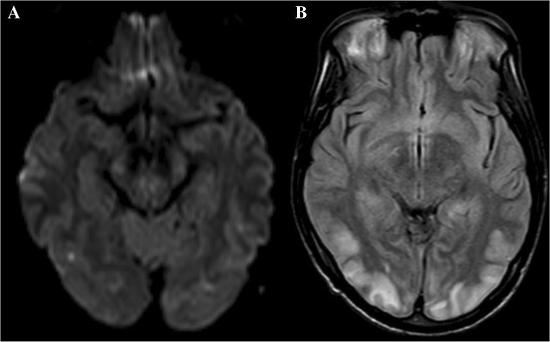

中风即“脑卒中”,是一种脑血管异常引发的脑部损伤,可分为脑出血和脑梗死两种类型,二者均可引发局部缺血和坏死。脑是神经系暴风怎么去潘达利亚统的“司令部”,脑部病变可引发任何身体异常,包括手部的感觉和运动功能异常。1、症状特点。一般情况下,手部的感觉和运动功能异常只是诸多中风症状的一部分,相关的症状可能还包括瘫痪、思维和意识异常、语言功能异常、行走功能异常、整个上肢功能异常等。在极为巧合的情况下,也可能仅仅出现手部症状,但一般不会像腕管综合征那样仅仅引发桡侧三指半的症状。当然,中风的精确诊断还是要依靠精密的脑部影像。

脑部核磁共振影像资料